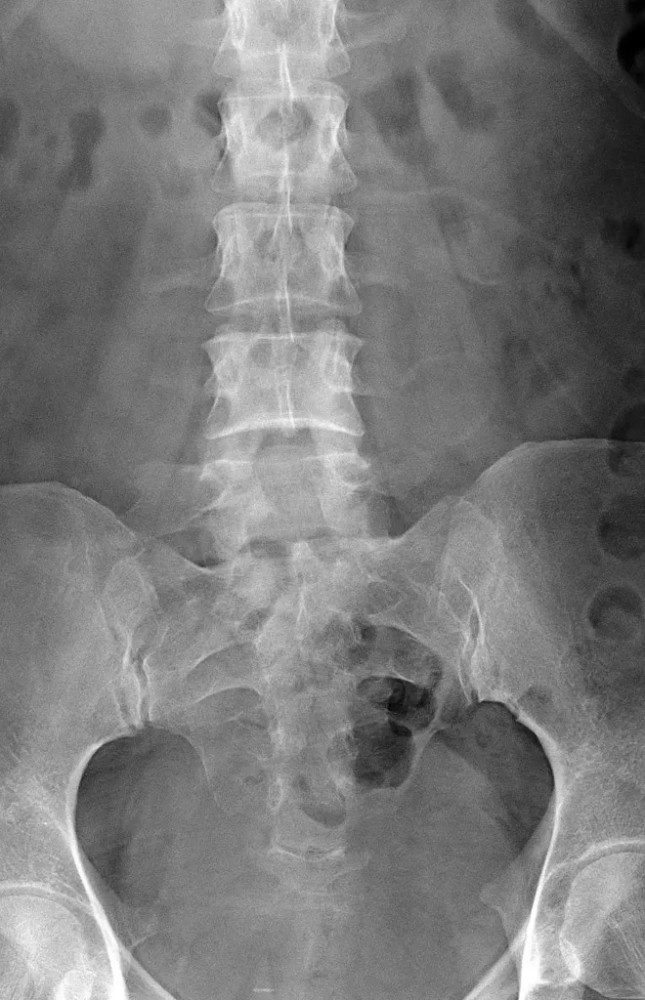

文章插图

腰椎正位片示:L5 椎体双侧横突肥大 , 为Ⅰb 型;